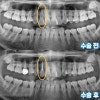

수술 전 수술 후 비교 사진, 20대 남성(2024/2 촬영)

수술을

성공적으로 마쳤습니다.

수술 직후 환자분의

파노라마 사진입니다.

전과 비교했을 때

치아 뿌리 근처 잇몸에

뼈가 채워진 모습이

보이시나요?

죽은 신경과 염증을

모두 제거하고

이제 검은 부분이

더이상 보이지 않습니다.